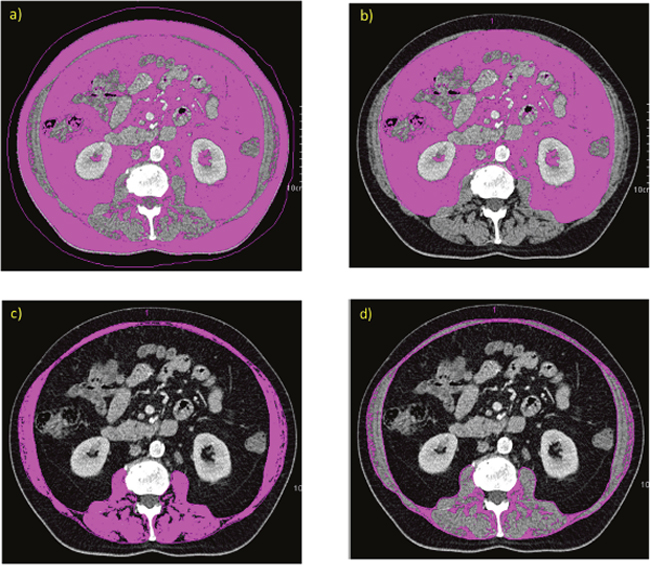

Figure 1: Example of densitometric quantification of adipose tissue area (threshold: -190 to -30 HU) in a CT scan at level L3/4: ROI determining TAT (a) and VAT (b). Example of densitometric quantification of muscle area in a CT-scan at level L 3/4 with ROI determining muscle compartments with threshold: -29 to +150 HU (c) and IMFA with threshold: -190 to-30HU (d).

Quantification of adipose tissue and muscle tissue via CT

We retrieved abdominal CT-scans from the institutional picture and archiving system (PACS, GE Medical Systems, Buckinghamshire, UK). Area-based quantification of adipose tissue compartments was conducted on one representative image slice at level between vertebral-body L3/4 using a semiautomatic software tool (Syngo Volume tool, Siemens Healthcare, Munich, Berlin, Germany) [54]. By manually defining regions of interest (ROI), the total-adipose-tissue (TAT, whole circumference of abdomen) and the visceral-adipose-tissue (VAT, marking the abdominal wall along the fascial plane) were quantified (volumetric measurement of selected slice, divided by slice thickness) as preformed in previous studies [31]. Measurement thresholds with a lower attenuation limit of -190 HU and an upper attenuation limit of -30 HU were chosen to selectively measure adipose tissue within these ROIs as previously described [31, 55]. By subtracting VAT from TAT subcutaneous adipose tissue (SAT) was calculated. The visceral-to-subcutaneous-fat ratio was calculated as VFA/SFA.

On the identical image slice (L3/4) a ROI containing all muscles (M.erector spinae, M.psoas major, M.latissimus dorsi, M.quadratus lumborum, M.transversus abdominis, M.obliquus abdominis externus and internus abdominis and M.rectus abdominis) was manually defined (volumetric quantification of selected slice, divided by slice thickness) [31, 32]. Muscle tissue was selected by limiting the measurements to a lower attenuation limit of -29 HU and an upper attenuation limit of 150 HU (MA150, Figure X) [32, 56, 57]. To measure only adipose tissue within muscle compartments (inter-muscular-fat-area, IMFA) a limit of -190 to -30 HU was chosen [32]. Mean muscle density in HU of each ROI was recorded (MD) and skeletal-muscle-index (SMI) was defined as SMI=muscle150/(height2) with the unit cm2/m2 [56, 58]. An exemplary image of the CT-based body composition quantification is shown in Figure 2.